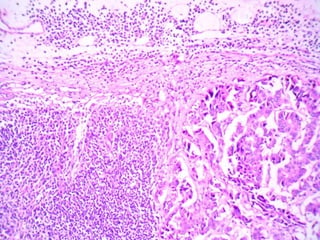

A 55-year-old female presented with pancytopenia and spleenomegaly. Bone marrow aspiration was dry but imprint smears and biopsy showed relevant findings. A 30-year-old male presented with upper GI obstruction and was found to have an ulcerative duodenal lesion. He underwent Whipple's operation and imaging found enlarged pancreaticoduodenal and paraaortic nodes with mild hepatosplenomegaly. Micrographs of lymph nodes were submitted. A 65-year-old male presented with abdominal discomfort and CT scan showed multiple enlarged retroperitoneal and mesenteric nodes without hepatosplenomegaly; a biopsy of a retroperitoneal lymph node was submitted.